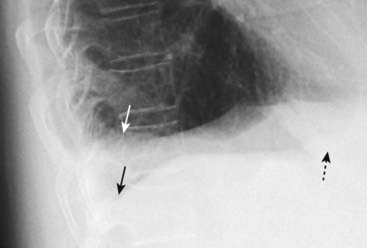

Figure 6-1 Dressler syndrome (postpericardiotomy/postmyocardial infarction syndrome).

A left pleural effusion (A) is present (solid black arrows). This syndrome typically occurs 2 to 3 weeks after a transmural myocardial infarct. It also can occur following pericardiotomy such as occurs in patients undergoing coronary artery bypass surgery, as in this case. The combination of chest pain and fever, left pleural effusion, patchy left lower lobe airspace disease, and pericardial effusion several weeks following a myocardial infarction or open-heart surgery should suggest the syndrome. It usually responds to high-dose aspirin or steroids. This patient has a dual lead pacemaker in place and, on the lateral projection (B), the leads are seen in the region of the right atrium (dotted black arrow) and right ventricle (arrowhead).